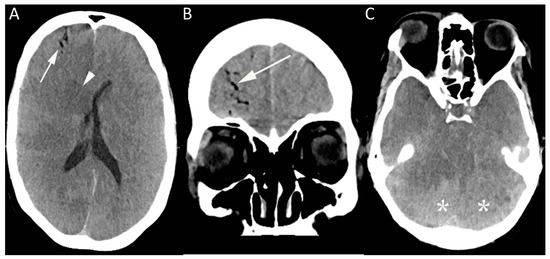

When all locations were included, vascular access-related procedures were most commonly associated with air embolism. In addition to the nine cases related to line placement described above, 13 cases were noted to have occurred during the use or removal of vascular access (Figure 1; Table 3), including two cases of inadvertent air bolus administered via intravenous lines.

Figure 1.

This image shows a computed tomography (CT) brain of a 50-year-old female in the medical intensive care unit who became unresponsive shortly after removal of an internal jugular line. CT brain (A–C) was performed showing gas within the right frontal lobe in distribution, suggesting an intravascular location (arrow, A and B), together with diffuse loss of gray-white matter differentiation, most prominently in the central deep nuclei (arrowhead). There was evidence of mass effect, with effacement of the basal cisterns (C), and the dense cerebellum sign (*) related to relative sparing of the cerebellar hemispheres.